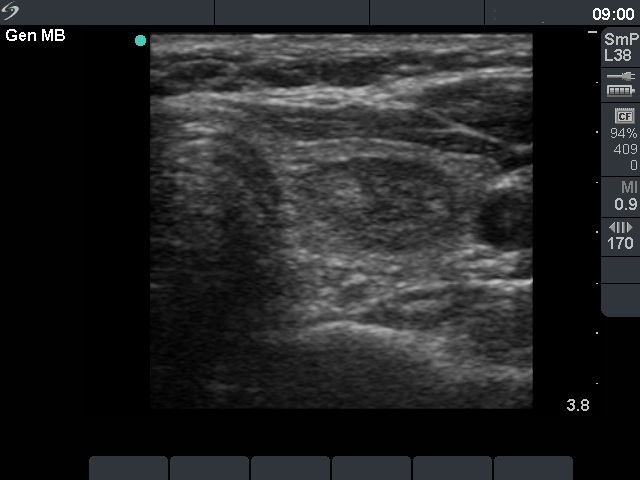

First examination (1st and 2nd rows of images)

Clinical presentation: a 45-year-old woman was referred for evaluation of a nodule discovered by carotid Doppler examination.

Palpation: a not firm nodule in the left lobe.

Functional state: euthyroidism with TSH-level 1.33 mIU/L.

Ultrasonography. The thyroid was echonormal. There was a moderately hypoechogenic, inhomogeneous nodule in the part of the left lobe. The nodule presented a type 3 vascular pattern.

Cytological pattern corresponded to a follicular tumor without significant atypia.

A combined clinical-ultrasound-cytological diagnosis was benign follicular proliferation with less than 1% risk of carcinoma.

We advised regular follow-up instead of immediate surgery.